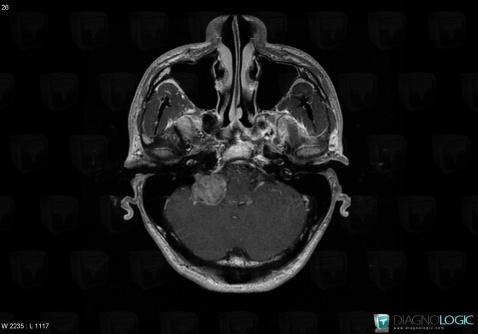

Schwannome, Espaces peri cérébraux infratentoriels, Autres nerfs craniens, IRM

Voici les informations spécifiques à l'image clé ci dessus:

- Diagnostic Schwannome, Localisation(s) Autres nerfs craniens, comportant les gammes Lésion des nerfs craniensEspaces peri cérébraux infratentoriels, comportant les gammes Lésion extra axiale infra tentorielleFosse postérieure, comportant les gammes Lésion infratentorielle en hypersignal T2 ou FLAIR